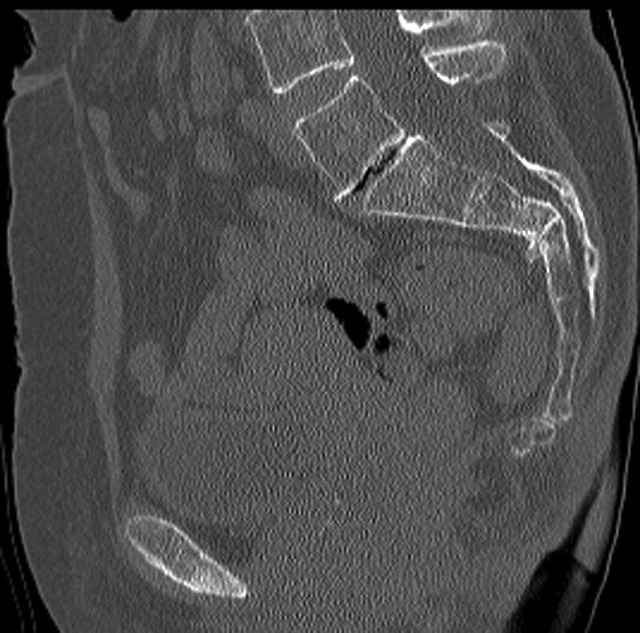

Here are a recent patient’s example slides...

54 yo Female Fell c/o Pain

Pelvic CT Scan - 3 Months After Fall

Sacral Injuries

Ramus Fractures

Percutaneous Fixation

(B) Ramus-Retrograde

2 TransIliac-TransSacral

Upper Segment